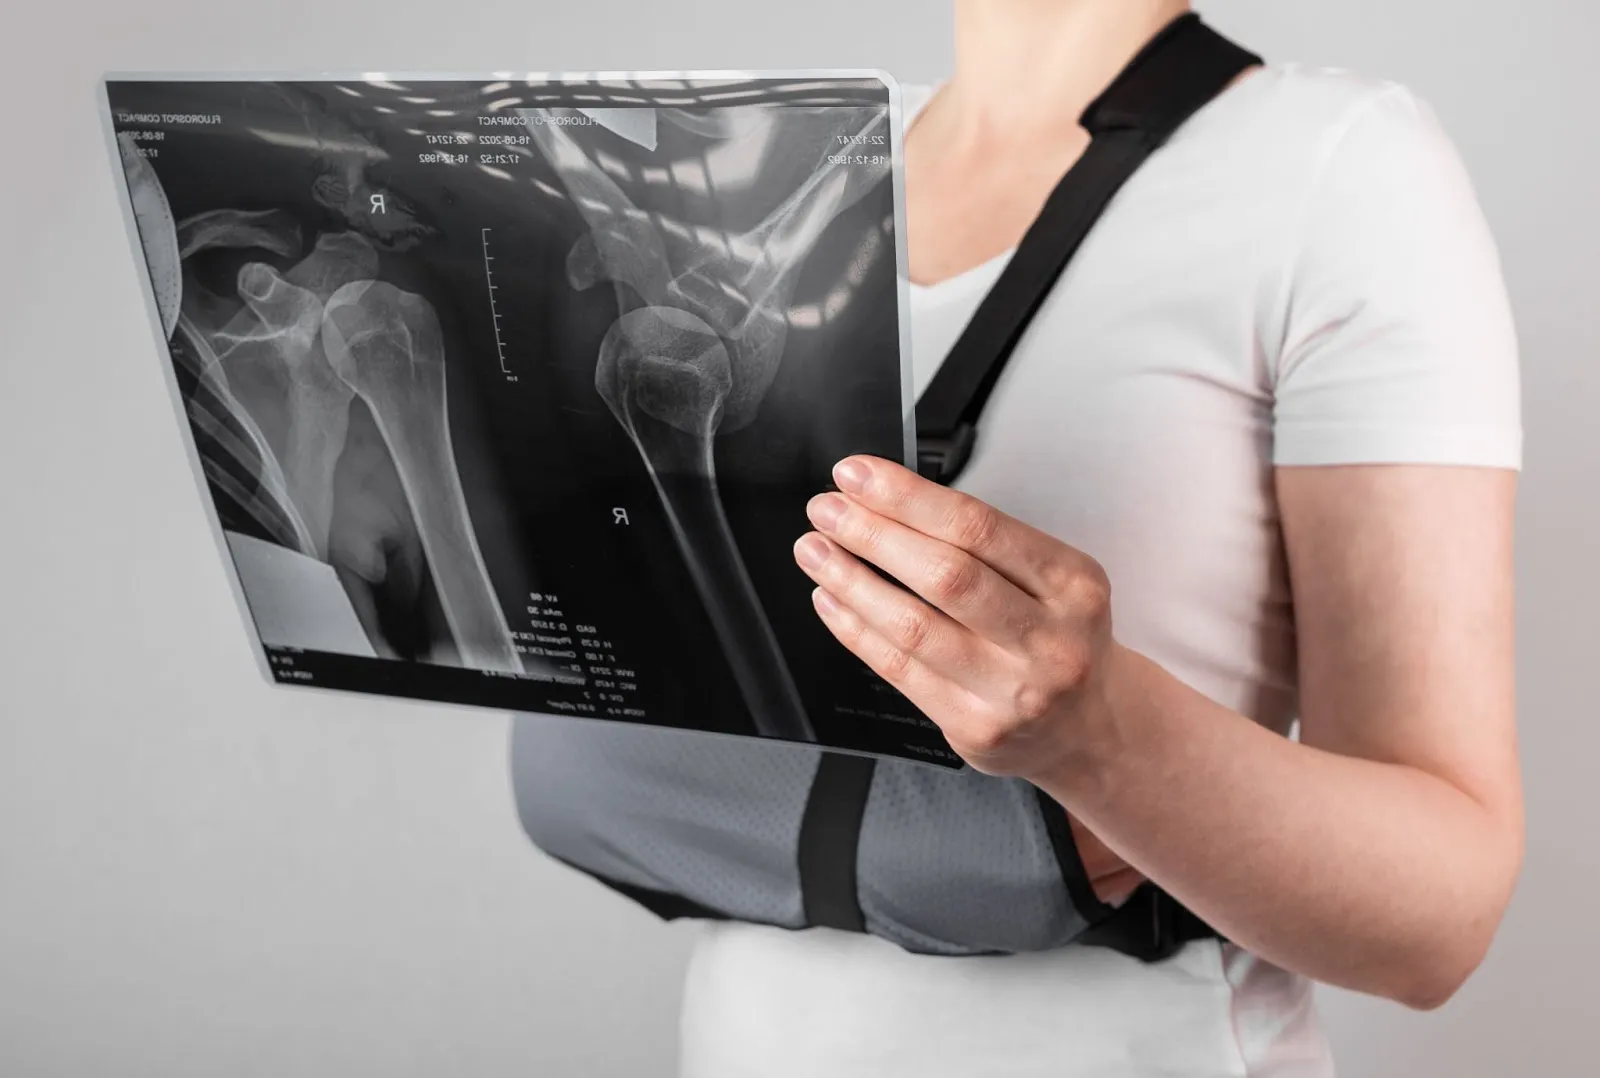

상완골 골절 핀제거, 상완골 골절 치료기간, 상완골 골절 재활 (어깨뼈 골절 수술후 재활치료)

상완골 골절은 팔의 기능을 담당하는 핵심 뼈가 손상되는 질환으로, 단순 골절부터 분쇄 골절까지 다양한 형태로 발생합니다. 특히 교통사고나 낙상, 스포츠 손상 등 외상에 의해 발생하는 경우가 많으며, 치료 과정은 단순히 뼈를 붙이는 것에서 끝나지 않고 재활까지 이어지는 장기적인 관리가 필요합니다.

상완골 골절이란 무엇인가

상완골은 어깨부터 팔꿈치까지 이어지는 긴 뼈로, 어깨관절과 팔꿈치관절을 연결하는 핵심 구조입니다. 이 부위가 골절되면 단순한 통증을 넘어서 팔의 움직임 자체가 제한되며 일상생활에 큰 불편을 초래합니다.